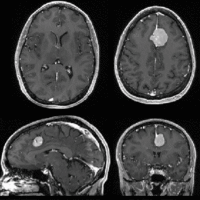

Intra-subject Brain MRI: axial T1 Tumor Growth Assessment

| fixed image/target | moving image |

This is a classic case of change assessment. We want to know if the tumor changed since last exam.

- reference/fixed : T1 SPGR , 0.9375 x 0.9375 x 1.4 mm voxel size, axial, RAS orientation.

- moving: T1 SPGR , 0.9375 x 0.9375 x 1.2 mm voxel size, sagittal, RAS orientation.